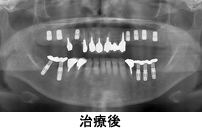

症例5

60代男性 全歯をインプラントで修復しました

治療期間:9ヵ月

価格:インプラント体 1本 22万円(かぶせもの別)、ブリッジ 片顎 75万円(税別)

この症例はインプラント体 15本 330万円、ブリッジ 上下1つずつ 150万円

合計:480万円(税別)

- 治療内容

- 残っている歯は重度の歯周病でした。全歯をインプラントで修復しました。インプラントの上部構造は固定式です。義歯に比べてしっかりかめて、動いたり痛んだりすることはありません。